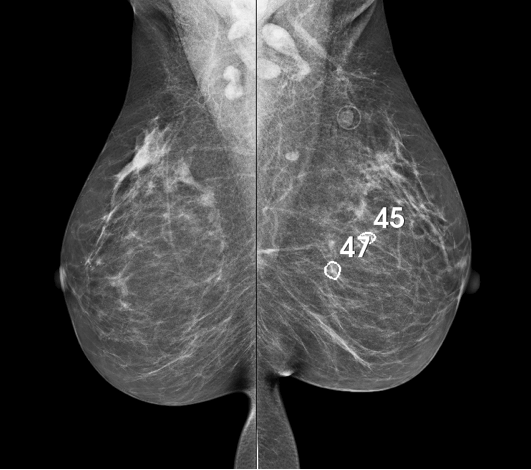

Στο κέντρο μας έχουμε εγκαταστήσει σύστημα τεχνητής νοημοσύνης για την ανίχνευση ύποπτων βλαβών στη μαστογραφία με τη βοήθεια της πλατφόρμας CAD, της εταιρείας Transpara, Screen Point Medical. Η νέα αυτή τεχνολογία, έχοντας μελετηθεί σε εκατοντάδες μαστογραφίες γυναικών με ή χωρίς παθολογικά ευρήματα, όπου η εγκυρότητα της τεχνικής είναι εντυπωσιακή, χρησιμεύει ως δεύτερο σετ ματιών και καίριο βοήθημα του ακτινοδιαγνώστη στη μάχη ενάντια στον καρκίνου του μαστού. Ένα άλλο σημαντικό πλεονέκτημα αυτής της τεχνολογίας είναι η δυνατότητα βαθμολόγησης των μαστογραφιών, με επισήμανση των περιπτώσεων υψηλού έναντι χαμηλού κινδύνου, πράγμα το οποίο μας βοηθά σημαντικά στην εφαρμογή ειδικών πρωτοκόλλων παρακολούθησης για τις γυναίκες που παρουσιάζουν αυξημένο κίνδυνο.

Εικόνα 1. Μαστογραφία με την εφαρμογή της τεχνητής νοημοσύνης, όπου οι ύποπτες περιοχές στον αριστερό μαστό έχουν επισημανθεί με κύκλους και έχουν βαθμολογηθεί ανάλογα με τον ενδεχόμενο κίνδυνο κακοήθειας.